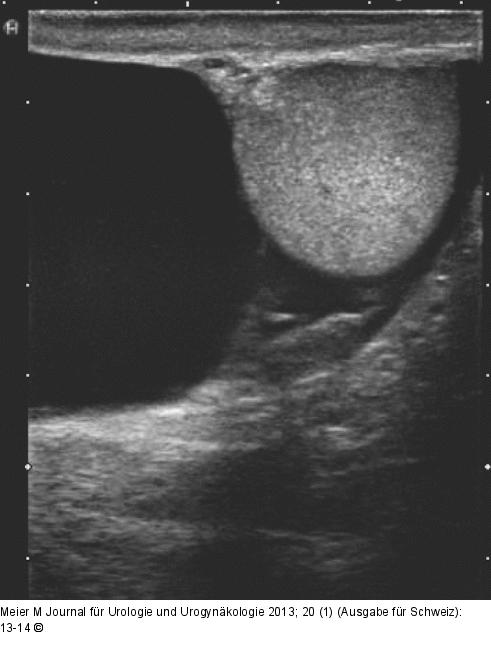

Abbildung 1: Hydrozele Sonographische Darstellung einer Hydrozele |